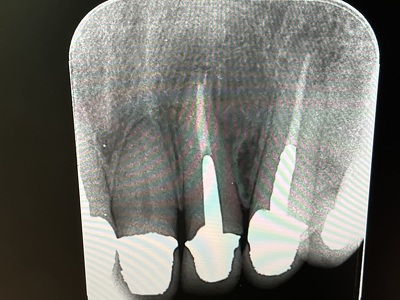

患者さんは静岡県からお出でになりました。レントゲン写真の右上2番の治療を依頼されました。

レントゲンでは上手く治療できているように見えますが治療結果は悪く、たびたび化膿を繰り返し、抜歯を進められていました。

当院で治療後のレントゲンです。根の尖にあった病巣が消失しています。